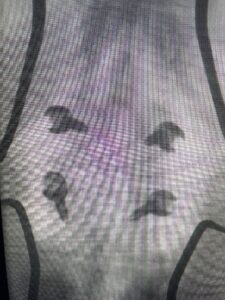

Another patient is a 62 year-old female with progressive low back pain and right leg pain and numbness that radiates to the top of her foot. She tried physical therapy and epidural injections. MRI demonstrated severe L3-4 stenosis and a grade 1 spondylolisthesis (Fig 4). There was L5-S1 and L4-5 disc collapse with modic end-plate changes. Biomechanically because of the significant degeneration of these disc spaces which stiffened the L4-S1 segment more stress was placed on the L3-4 segment, resulting in significant premature degeneration and compensatory stenosis and segmental instability. The MRI also showed pathologically, because of the slip, the L3 inferior processes were more anteriorly oriented and hence contributing to the majority of the lumbar canal compromise. Note the more sagittally-oriented facets in this case compared to the prior case (Fig 5). The patient underwent a decompressive laminectomy with attention of removing the inferior processes of L3 to fully decompress the canal. We also performed an L3-4 fusion with instrumentation (Fig 6). The patient had an uneventful postoperative course with improvement of leg pain. Of note with relief of the disabling leg pain patients are generally very happy. Patients can often manage their low back pain; it is the leg pain that they just can’t tolerate.

Fig 5 Axial T2-weighted lumbar MRI demonstrating significant L3 inferior facet contribution of severe stenosis (blue arrow)